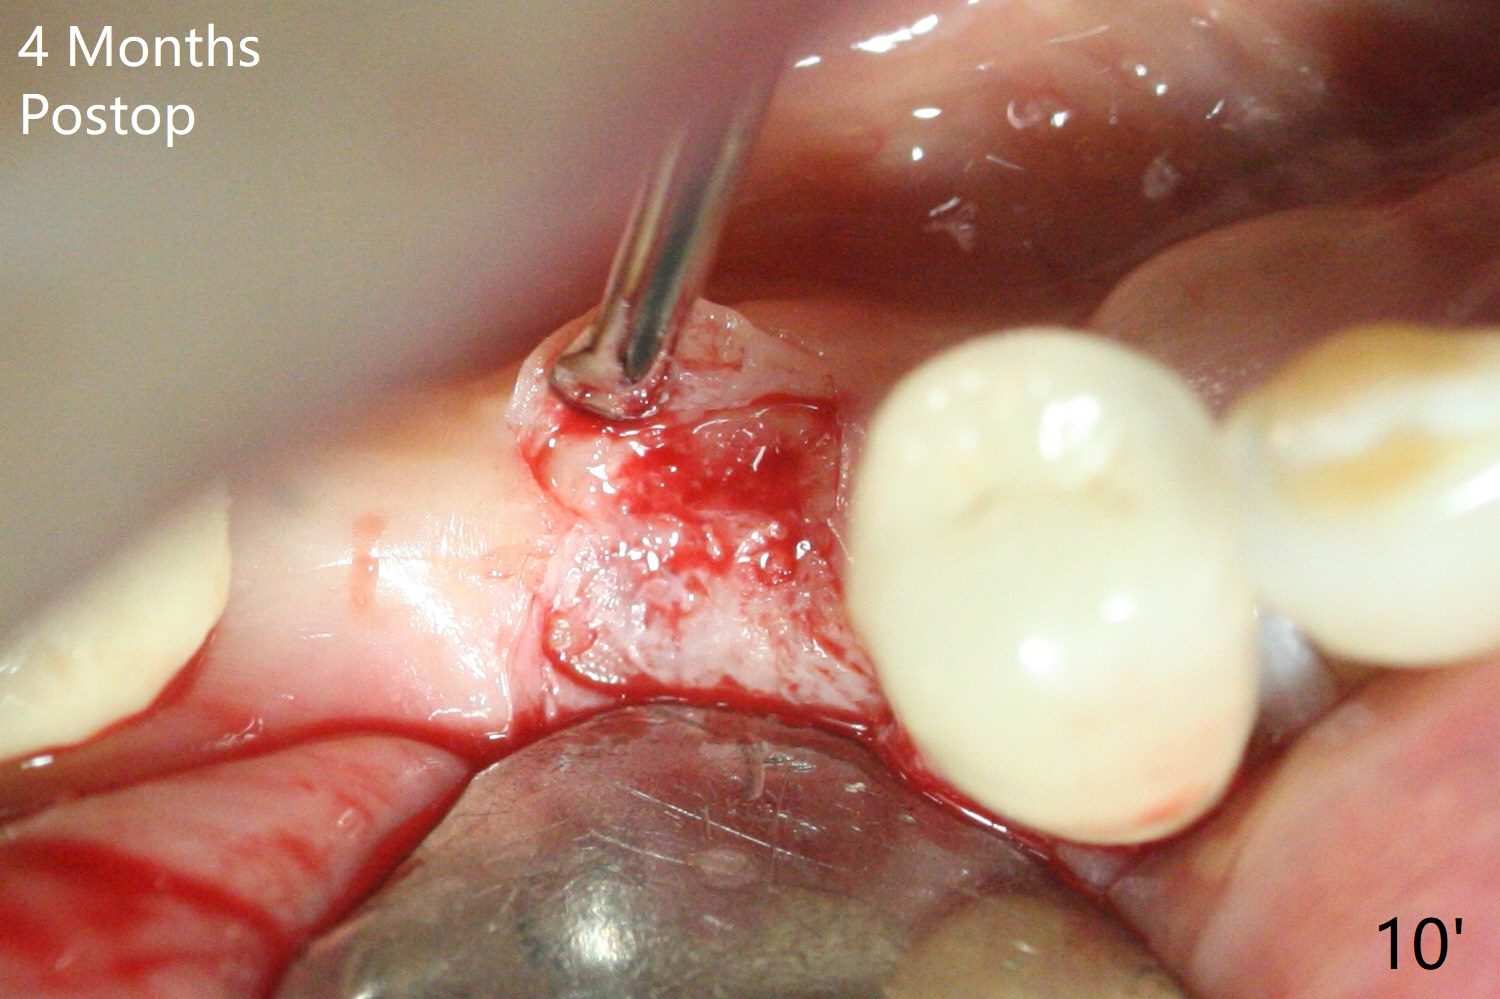

The keratinized gingiva at #29 is slightly lingual with torus mandibularis (Fig.1 *). 4 mm tissue punch through metal sleeve makes a superficial mark (Fig.4). To save the keratinized tissue, a lingual flap is designed as shown in Fig.4 insert (black line; avoiding the torus *). Osteotomy involving 4 mm cortical drill is related to <10 Ncm insertion torque of a 4x11 mm implant; a healing screw is placed (Fig.5 S). After removing the torus and placement of bone graft and collagen plug (Fig.6 *), the lingual flap is sutured in place without tension because of the torus resection (Fig.7 *). Later the wound is covered by periodontal dressing.

The extraction socket of #31 has a thin septum (Fig.2), which is removed partially with 12 mm bone trimmer (Fig.3). After placement of a 5x9 mm FC implant (~40 Ncm) and 6 mm bone profile drill, a 5.5x4(2) mm abutment is incompletely seated (Fig.5 <) and later is changed to a 4.5x1 mm temporary abutment (Fig.6, 8 T). The latter is used to fabricate a provisional, which in turn supports the distal papilla (Fig.8 *). The gingiva is slightly erythematous immediately post periodontal dressing removal (3 weeks postop, Fig.9). Take CT to confirm whether the cortical drill helps keep the #29 implant lingual. Use a profile drill at #29 if crestal bone loss is not obvious. There is bone coronal to #29 implant 4 months postop (Fig.10). Upon incision, the ridge is rounded (Fig.10'), but the implant appears to be buccally placed (Fig.10'' (post high speed handpiece and 5.5 mm profile drill)). The latter is confirmed by CT (Fig.12, as compared to design (Fig.11)). In spite of use of cortical drill coronally, the implant is still deviated buccally due to contrasting deferential bone density linguobuccally (Fig.13). By comparison, there is no such bone density differential involving an immediate implant at #31; the implant is placed in the socket without contacting the buccal or lingual cortices (Fig.14). The final implant is the same as expected (Fig.15). To avoid implant deviation in the lower premolar region, leave the root in place until osteotomy is finished. Five months postop, the temporary and healing abutments at #31 and 29 change to pair ones (Fig.16). Since there is limited clearance from the crestal bone, smaller abutments are used with the apparently same degree of seating (Fig.17). The abutments are prepared due to the mesial (#31) and buccal (29) tilt before impression.